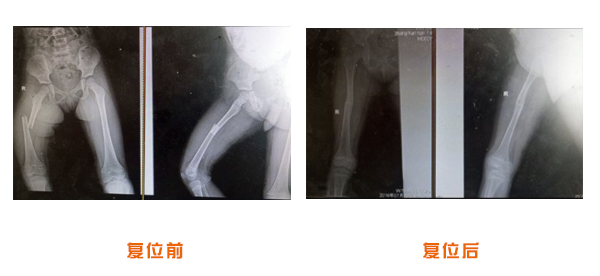

肥城市安駕莊梁氏骨科醫(yī)院是一所以梁氏手法正骨配合膏藥為特色的現(xiàn)代化??漆t(yī)院。

梁氏骨科術(shù)始創(chuàng)于清雍正年間,歷經(jīng)八代,至今已有三百年歷史。據(jù)1929年泰安縣志載“梁瑞圖先生,字增生,號蓮峰,安駕莊人,精岐黃并發(fā)明接骨,凡跌打車凡跌打車軋皮不破而碎骨者......【詳細】 |